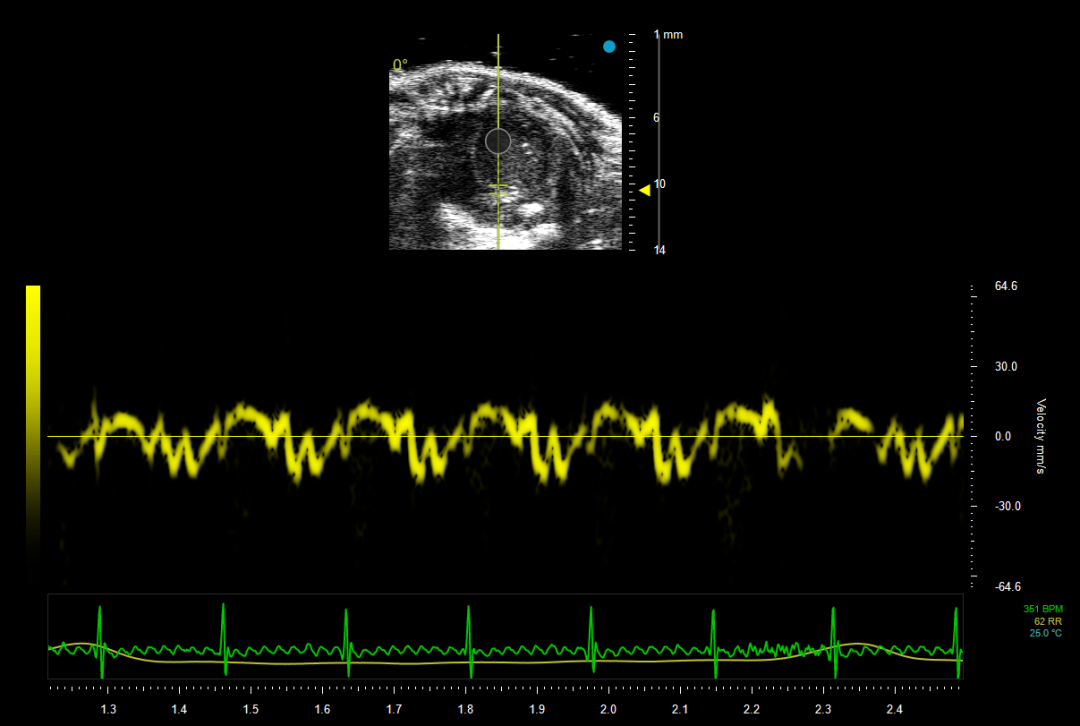

6. 再次点击转换为组织多普勒(Tissue Doppler Imaging,TDI/TD)模式,取样容积置于室间隔处二尖瓣瓣膜位置,获取二尖瓣瓣膜运动频谱,如图6所示,可以获取 e' 峰、a' 峰等参数。e' 峰代表舒张早期心肌运动速度峰,a' 峰代表舒张晚期心肌运动速度峰,直接反映心肌舒张和收缩功能。

图6 心尖四腔切面中二尖瓣瓣膜运动波谱

(Pulsed Wave Doppler)